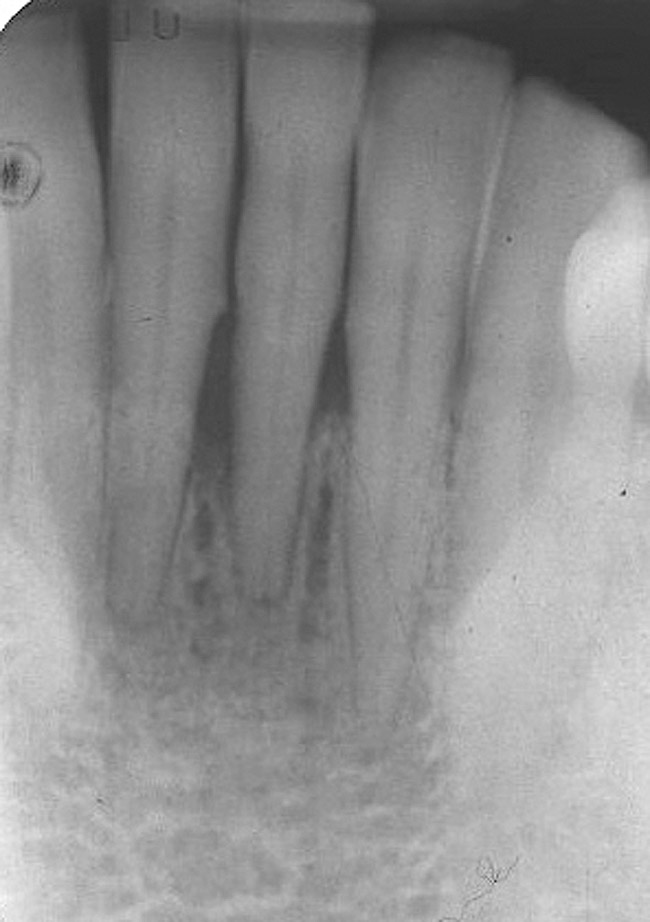

A 53-year-old male presented with localized advanced periodontal disease of the mandibular incisors. Teeth Nos. 23 to 26 exhibited Class II mobility because of advanced bone loss (Figure 1). The teeth had migrated out of position over the years, and a diastema had developed between No. 24 and No. 25 (Figure 2). The patient complained about the poor esthetic appearance of these teeth, and he was able to perceive their loss of strength on function as a result of their mobility.

Figure 2  Preoperative radiograph shows healthy cuspids and advanced periodontal disease on the four mandibular incisors.

Figure 2